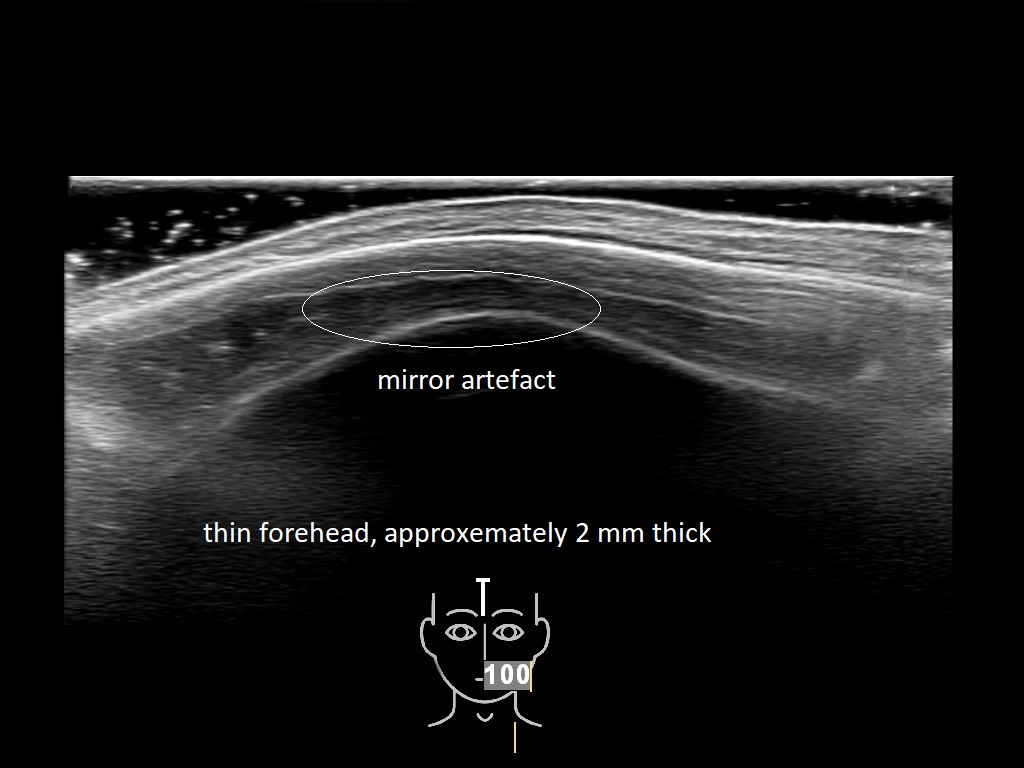

In this section you will learn more about the different layers of the face with the use of ultrasound. When you click on the secondary ultrasound image, you will see the different structures as an overlay. This will help to train yourself to recognize the different layers of the face.

Study the first image to recognize the different layers. If you are sure about the layers, swipe to the second image to view the answer (if applicable).